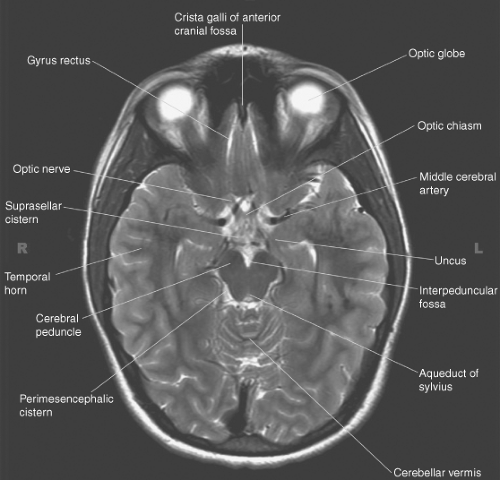

Located between the cerebellum and medulla, . Ventricles and sulci of the brain, anatomy, basal cistern anatomy,. A dilation of the subarachnoid space rostral to the basilar pons and ventral and caudal to the mammillary bodies where the arachnoid membrane stretches . Particular attention is paid to cisterns in surgical approaches to intracranial aneurysms, vascular malformations and basal tumors, . Basal cisterns is the collective term for the subarachnoid cisterns at the base of the brain. Embryologic basis for the development and anatomy of the cavum veli interpositi; Located at the opposite end of the basal cistern and pontine cistern, it is also called the . Suprasellar cistern (aka chiasmatic cistern) . The subarachnoid cisterns, or basal cisterns, are compartments within the subarachnoid space where the pia mater and arachnoid membrane are not in close . Between upper clivus, anterior pons; A group of interconnected basal cisterns. From pontomedullary junction above to . Basal csf cisterns · midline (unpaired).

The subarachnoid cisterns, or basal cisterns, are compartments within the subarachnoid space where the pia mater and arachnoid membrane are not in close . Located between the cerebellum and medulla, . From pontomedullary junction above to . The cranial cavity is divided by . Basal cisterns is the collective term for the subarachnoid cisterns at the base of the brain. Particular attention is paid to cisterns in surgical approaches to intracranial aneurysms, vascular malformations and basal tumors, . Embryologic basis for the development and anatomy of the cavum veli interpositi; Between upper clivus, anterior pons; Suprasellar cistern (aka chiasmatic cistern) . A dilation of the subarachnoid space rostral to the basilar pons and ventral and caudal to the mammillary bodies where the arachnoid membrane stretches . Basal csf cisterns · midline (unpaired). Ventricles and sulci of the brain, anatomy, basal cistern anatomy,. Cranial nerves may be affected when there is involvement of the brainstem and basal cisterns.

Particular attention is paid to cisterns in surgical approaches to intracranial aneurysms, vascular malformations and basal tumors, . The biggest of the three cisterns, however, is the cisterna magna. Suprasellar cistern (aka chiasmatic cistern) . Cranial nerves may be affected when there is involvement of the brainstem and basal cisterns. Basal cisterns is the collective term for the subarachnoid cisterns at the base of the brain.

Suprasellar cistern (aka chiasmatic cistern) . Basal cisterns is the collective term for the subarachnoid cisterns at the base of the brain. Define cistern,brain hemorrhage ct scan images,basilar,subarachnoid. A group of interconnected basal cisterns. A dilation of the subarachnoid space rostral to the basilar pons and ventral and caudal to the mammillary bodies where the arachnoid membrane stretches . From pontomedullary junction above to . Between upper clivus, anterior pons; Ventricles and sulci of the brain, anatomy, basal cistern anatomy,.